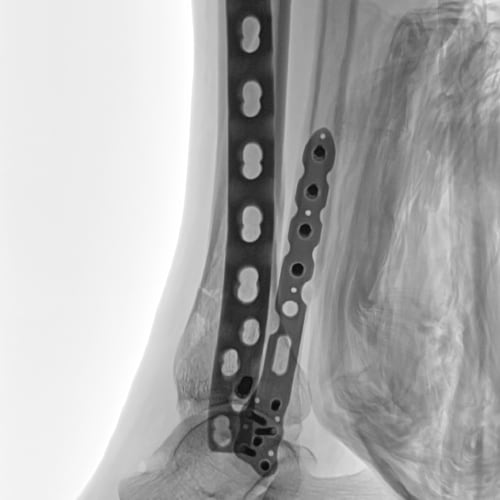

Metal correction

Minimizing halation for clear visualization in orthopedic procedures with bolts and implants.

No metal correction